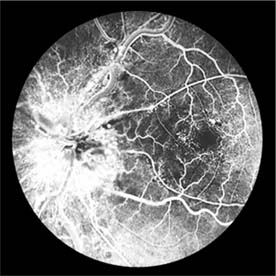

The appearance of the fundus in hypertensive retinopathy is determined by the degree of elevation of the blood pressure and the state of the retinal arterioles. Thus, in young patients with accelerated hypertension, an extensive retinopathy is seen, with hemorrhages, retinal infarcts (cotton-wool spots), choroidal infarcts (Elschnig's spots), and occasionally serous detachment of the retina (Figure 15-10). Severe disk edema is a prominent feature. Vision may be impaired but is restored if blood pressure is reduced with caution.

Figure 15-10: Accelerated hypertension. Fluorescein angiogram in a young man showing arteriolar constriction, dilation of capillaries with microaneurysms, and areas of closure. Marked disk edema is present.

In contrast, elderly patients with arteriosclerotic vessels are unable to respond in this manner, and their vessels are thus protected by the arteriosclerosis. It is for this reason that elderly patients seldom exhibit florid hypertensive retinopathy (Figure 15-11).

Figure 15-11: Accelerated hypertension. Fluorescein angiogram in an elderly wom.an showing marked arteriolar constriction and irregularity but few signs of florid retinopathy.

Fluorescein angiography has made possible accurate documentation of these microcirculatory changes. In young patients with hypertension, arteriolar attenuation and occlusion are seen, and capillary nonperfusion can be verified in relation to a cotton-wool spot, which is surrounded by abnormal dilated capillaries and microaneurysms with increased permeability on fluorescein angiography.